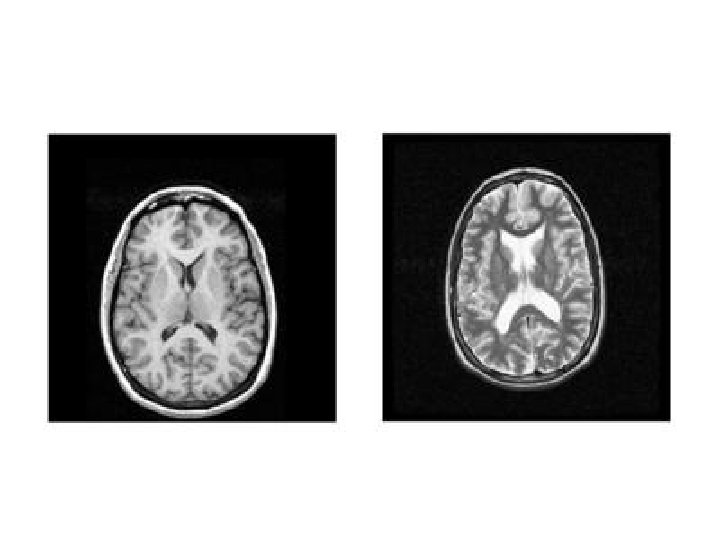

L'exploration fonctionnelle par l'imagerie cérébrale Premier tracé EEG de 1924 L'enregistrement de l'activité neuroélectrique chez l'être humain débutera avec l'apparition de l'électro-encéphalographie (EEG). Cette examen reste incontournable pour le diagnostic et la classification des épilepsies. IRM cérébrale Ce fut d'abord le scanner qui permet de visualiser, pour la première fois le cerveau et les zones corticales avec une précision remarquable, puis l'imagerie par résonance magnétique ou (IRM) a considérablement modifié, à son tour, l'étude iconographique des structures corticales.